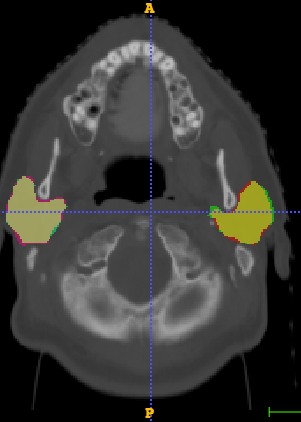

In Chapter 6, we propose an end-to-end, atlas-free 3D convolutional deep learning framework for fast and fully automated whole-volume HaN anatomy segmentation [115]. Our deep learning model, called AnatomyNet, segments OARs from head and neck CT images in an end-to-end fashion, receiving whole-volume HaN CT images as input and generating masks of all OARs of interest in one shot. AnatomyNet is built upon the popular 3D U-net architecture, but extends it in three important ways: 1) a new encoding scheme to allow auto-segmentation on whole-volume CT images instead of local patches or subsets of slices, 2) incorporating 3D squeeze-and-excitation residual blocks in encoding layers for better feature representation, and 3) a new loss function combining Dice scores and focal loss to facilitate the training of the neural model. These features are designed to address two main challenges in deep-learning-based HaN segmentation: a) segmenting small anatomies (i.e., optic chiasm and optic nerves) occupying only a few slices, and b) training with inconsistent data annotations with missing ground truth for some anatomical structures. We collect 261 HaN CT images to train AnatomyNet, and use MICCAI Head and Neck Auto Segmentation Challenge 2015 as a benchmark dataset to evaluate the performance of AnatomyNet. The objective is to segment nine anatomies: brain stem, chiasm, mandible, optic nerve left, optic nerve right, parotid gland left, parotid gland right, submandibular gland left, and submandibular gland right. Compared to previous state-of-the-art results from the MICCAI 2015 competition, AnatomyNet increases Dice similarity coefficient by 3.3% on average. AnatomyNet takes about 0.12 seconds to fully segment a head and neck CT image of dimension , significantly faster than previous methods. In addition, the model is able to process whole-volume CT images and delineate all OARs in one pass, requiring little pre- or post-processing. We demonstrate that our proposed model can improve segmentation accuracy and simplify the auto-segmentation pipeline. These contributions are released as an open-source software package called AnatomyNet, which is publicly available555https://github.com/wentaozhu/AnatomyNet-for-anatomical-segmentation. Portions of this chapter were published as part of [115].